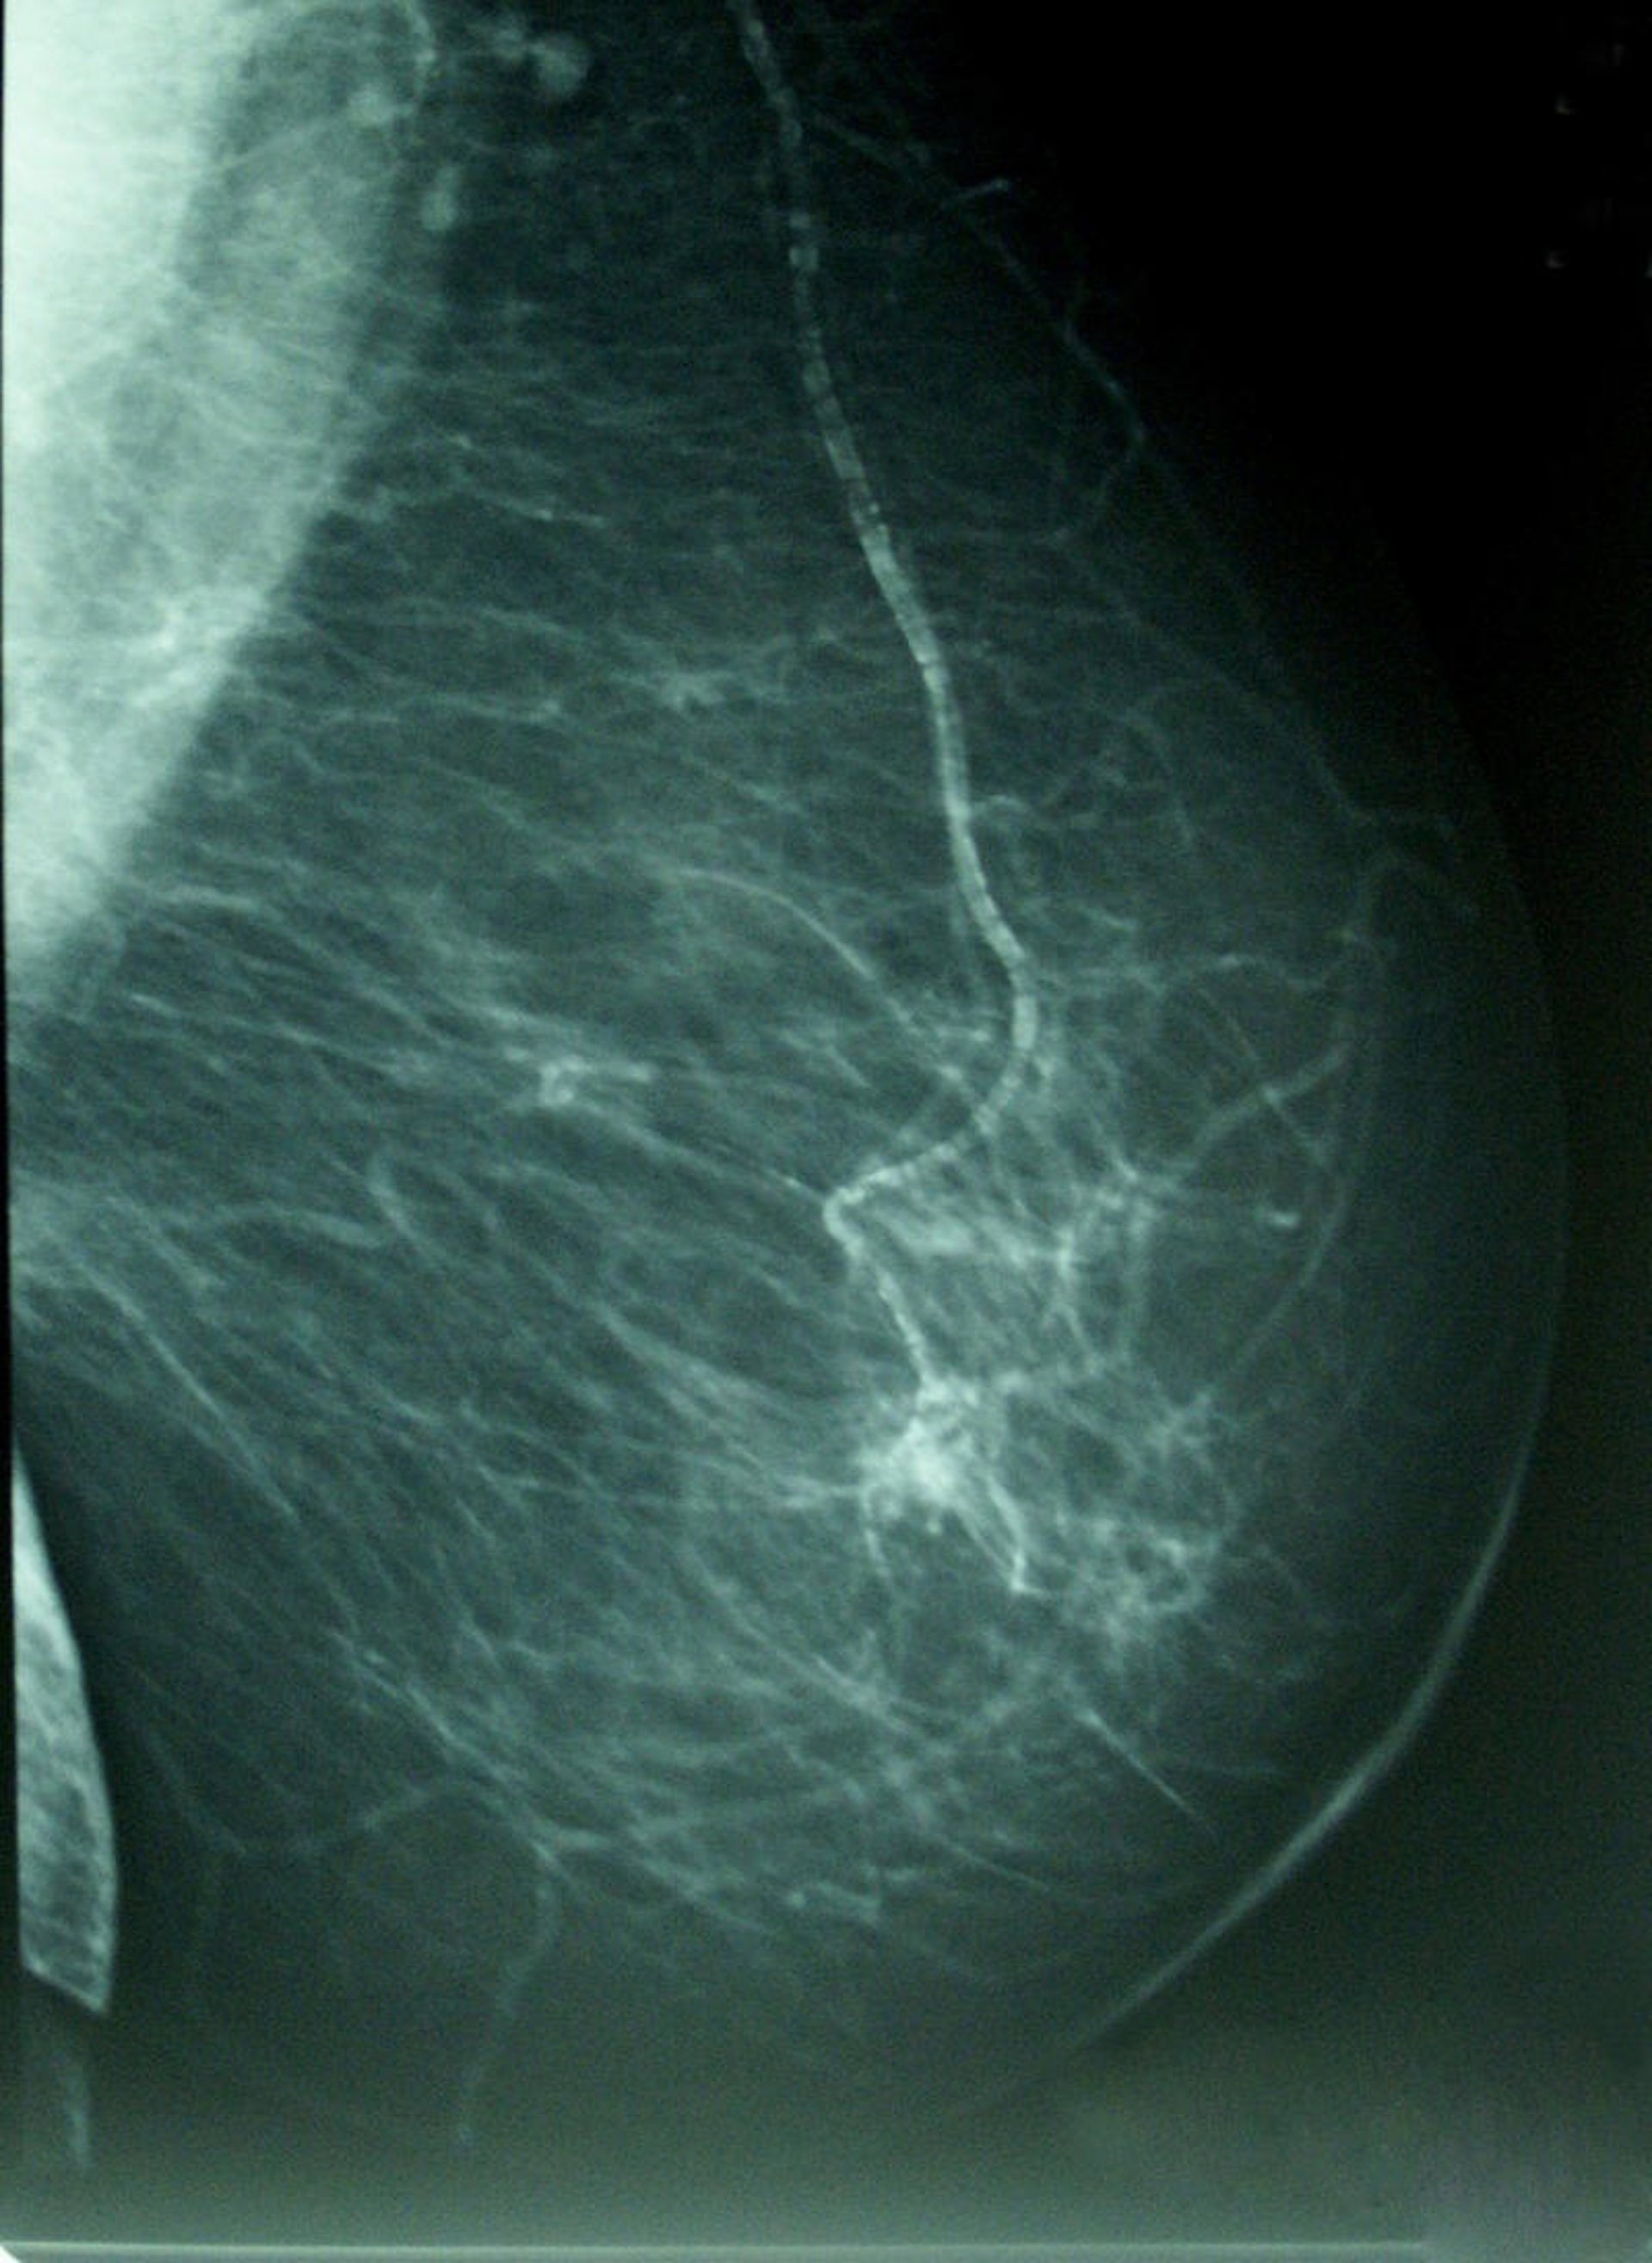

Cáncer De Mama, Densidad Mamográfica

Los datos poblaciones, no obstante, señalan que la incidencia de este tipo de cáncer se estabilizó en el periodo 1993-2007, a la vez que se redujo la mortalidad en un 3,7% anual; mientras que en el periodo 2000-2004 aumentó la tasa de supervivencia más allá de los cinco años hasta el 84% de los casos, gracias especialmente al diagnóstico precoz, el cribado mediante la mamografía y a las mejoras en los tratamientos.

Según la Encuesta de Salud de Cataluña de 2011, el 91,2% de las mujeres entre 50 y 69 años se realiza una mamografía de forma periódica, un año en el que más de 386.000 mujeres se realizaron esta prueba clínica.